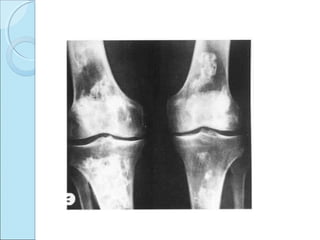

RADIOGRAPHIC FEATURES.RADIOGRAPHIC FEATURES.

PLAIN RADIOGRAPHS

 May be normal.

 When visible

=radiolucent ring surrounding bony fragment.

=in profile-loose body opposite to pit in bone.

Loss of sharp cortical line of articular surface.

X-ray knee frontal view---radiolucent line on lateral aspect

of medial condyle extending up to articular surface. Joint

space normal.